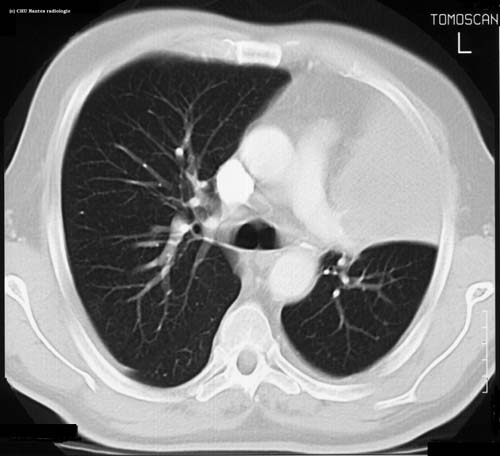

Atélectasie

niveau de la coupe

TDM